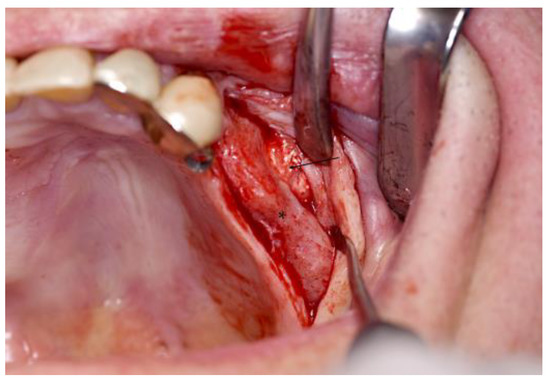

2. Case Presentation

3.1. Handling of the Scaffolds and Clinical Outcome